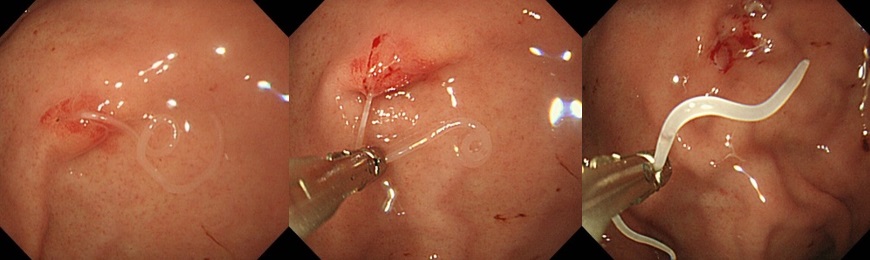

『サバ摂取後に寄生したアニサキスの摘出術』

大腸ポリープ切除術、早期癌に対する内視鏡的粘膜剥離術、胃潰瘍などからの出血に対する内視鏡的止血術、食道静脈瘤からの出血に対する結紮術、アニサキス(寄生虫)や薬パッケージの誤飲に対する異物摘出術など。また胆道・膵臓系では、内視鏡を用いた胆石除去や、胆道感染や癌に伴う黄疸に対する内視鏡的な減黄術(ステント留置術)など各種行っております。